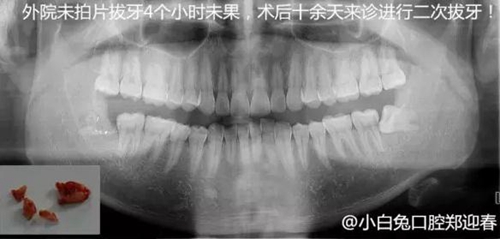

下邊也是一個斷根病例

遇到斷根怎么辦?我的觀點:拔!但有個前提,必須保證安全,否則寧可保留,因此拔牙前的溝通很重要!